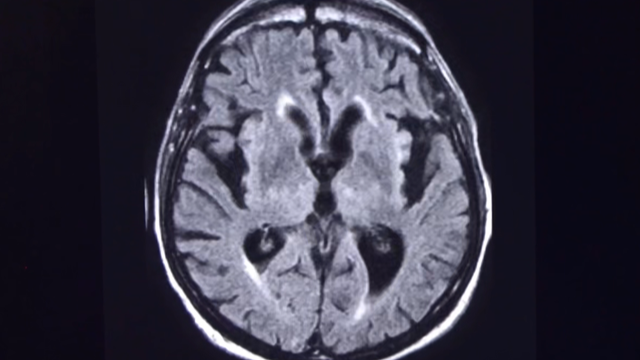

早期的氣球里面裝的都是氫氣,但是氫氣太危險了,有關部門如今已經禁止使用氫氣填充氣球。今天我們見到的氣球里絕大多數填充的都是氦氣。氦氣對中國這樣的工業大國來說異常重要。中國每年大約需要進口價值2億美元,總計4000噸的氦氣,這個數量的確不多,甚至還不到中歐之間每天貿易額的一個零頭。但氦氣的作用實在太大了,中國每年進口的4000噸氦氣里有30%都用在了醫療領域,主要就用在磁共振設備上,因為液氦的溫度接近絕對零度,所以當仁不讓就成了磁共振設備超導線圈的冷卻劑。